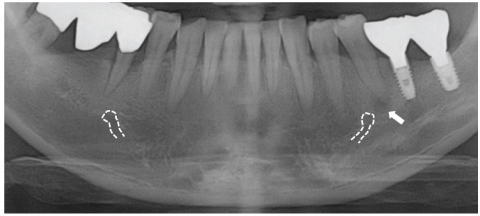

Figure 2

Preoperative panorama view. Periapical radiolucency was observed at the apex of mandibular left second premolar.

Location of mental foramens (dotted line) and periapical radiolucency (arrow).

Figure 2 Preoperative panorama view. Periapical radiolucency was observed at the apex of mandibular left second premolar.

Figure 4 Location of mental foramens (dotted line) and periapical radiolucency (arrow).